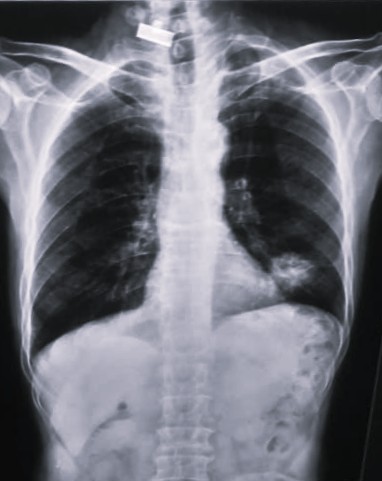

| 206 | IGGMC, Nagpur, Nagpur | P2 | 29-4266 | SHUBHAM URKUDE | Consent taken on Paper | 30 Yrs. |

Provisional Diag : PTB?

Final Diag : CLINICALLY DIAGNOSED PTB WITH OLD EPTB WITH LOSS TO FOLLOW UP IN CHRONIC ALCOHOLIC |

TB Case (Confirmed) | BILATERAL MIDDLE ZONE HAZZINESS/CONSOLIDATION | Abnormality visible on x-ray |